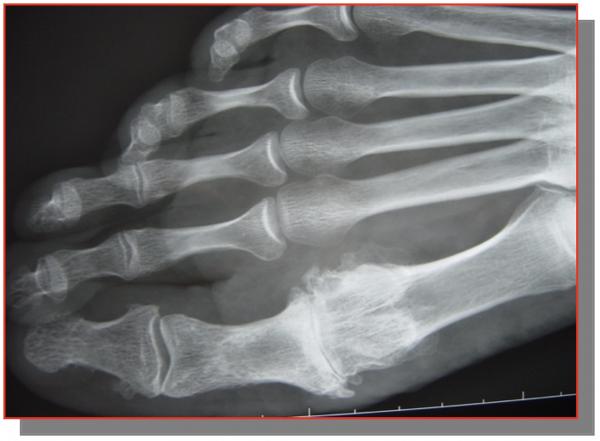

METATARSALGIES STATIQUES

Les métatarsalgies sont la conséquence d’un excès de contraintes mécaniques sous l’avant pied et en particulier sous les tètes métatarsiennes. Celles-ci se traduisent cliniquement par des phénomènes douloureux et des durillons plantaires, témoins cutanés des contraintes mécaniques excessives.

Un rappel biomécanique : tous les metatarses sont sollicités dans le plan sagittal l’angle d’attaque au sol est dégressif

DIAGNOSTIC

L’origine des métatarsalgies est multiple

C’est la traduction d’une défaillance d’une structure anatomique assurant la transmission des contraintes mécaniques du segment jambier vers les orteils et le sol.

Elles peuvent être la conséquence d’un problème local, (par exemple un hallux valgus) C’est le cas sur un problème anatomique de longueur ou de verticalisation des métatarsienslateraux en particulier au niveau 2 éme orteil qui créer le syndrome du 2 éme rayon

Ou provenir d’un problème à distance (par exemple une raideur de la cheville, un pied creux...).

QUE FAIRE ?

Radiographie des pieds face et profil en charge +++ avant consultation d’un spécialiste

Étude de l’architecture global du pied, de l’état articulaire à la recherche d’une arthrose, fracture de contrainte, et mesure des angles

On peut avoir recours aux scanners, échographies et IRM pour confirmer les lésions des articulations, des tendons, des plaques plantaires